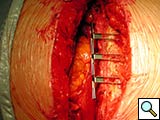

Figure 5. Technique of implantation: the two pliable vertical "fingers" of each unit are bent outwards around the ribs.

To facilitate insertion of the device, the fascia is dissected from the sternal border with electrocautery, and if necessary, perforating vessels are clipped (Figure 2). Once the fascia is mobilized, the hemisternum is elevated by two hand retractors to optimize exposure. The clips are assembled to form a device of a suitable length (up to 5 clips for each one) and the vertical segments of the clips are inserted into the intercostals spaces (Figures 3, 4). The two pliable vertical “fingers” of each unit are then bent outwards to wrap around the ribs, so that the clips are held firmly in place (Figure 5; Video 3). Re-approximation of the sternum is then achieved by means of single interrupted stainless steel wires. Two to 3 are placed through the manubrium, and the others are placed around the grooved arms of the clips at the level of the intercostal spaces (Figures 6, 7). The fascia, subcutaneous layers, and skin are closed in a routine manner. The extra time required for placement of the reinforcement device decreases with experience, and in our hands is approximately 4 to 6 minutes for each hemisternum.